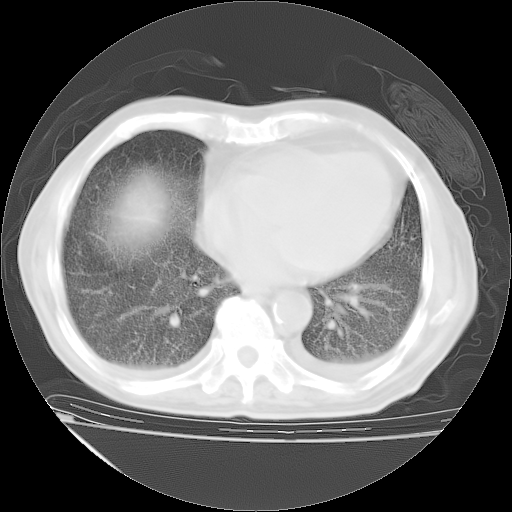

甲强龙80mg/日+抗结核治疗(异烟肼+利福霉素+乙胺丁醇)10天。复查肺部CT。

治疗10天肺部CT